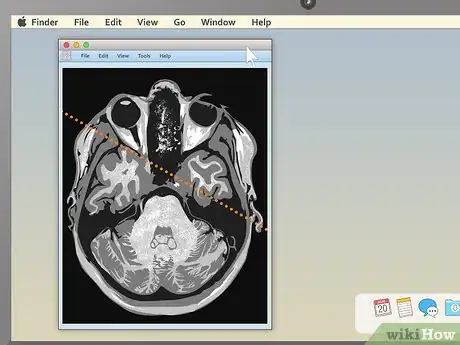

4Use the section-cut line to see where cross-sections are located. If you display a cross-sectional image along with a sagittal or coronal image, you may see a section-cut line on the second image. This will be a straight line running through the image, but it may not be present on all MRIs. If your image does have one, this shows where on the second image the cross section is located. You should be able to move the section cut line toward the center, right or left of the image. This will change the larger layout image to show the body from the new direction of the scan.

- The section-cut line on the layout picture also shows the direction that the image was taken from. For example, if your MRI were a picture of an everyday object, like a tree, the section cut line might show you if the picture was taken from above in a plane, from a second-story window, or from the ground.

-

5Drag the section-cut line to view new parts of the study. Dragging the section-cut line to a different part of the image allows you to "move around" your MRI images. The image should change your view to the new area automatically.

- For example, if you're viewing a sagittal image of your spine along with a cross section of one of your vertebrae, moving the section-cut line may allow you to cycle up and down through the various vertebrae above and below it. This can be useful for locating problems like herniated discs.